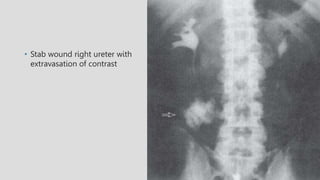

• Stab wound right ureter with

extravasation of contrast